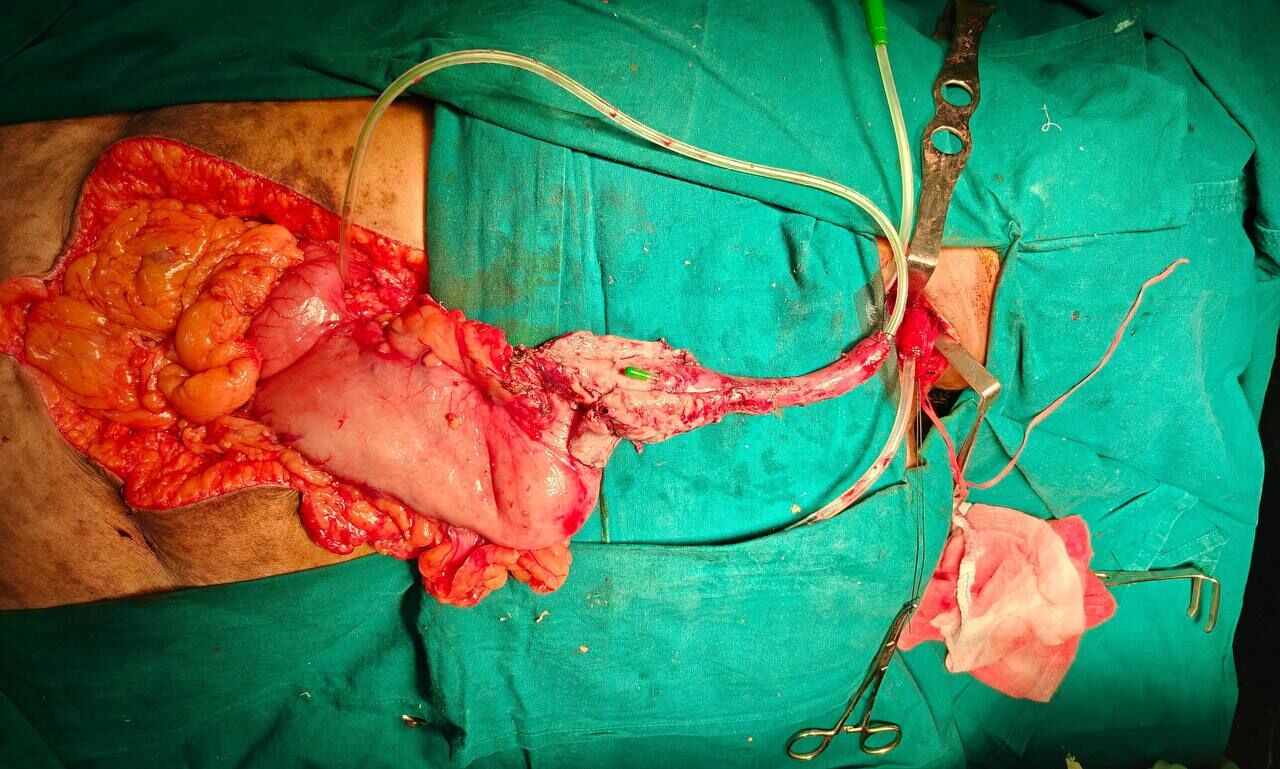

Given that the patient remained hemodynamically stable but showed progression of local sepsis, she underwent an emergency transthoracic esophagectomy with gastric conduit reconstruction. The procedure allowed definitive control of the source of contamination and restoration of gastrointestinal continuity.